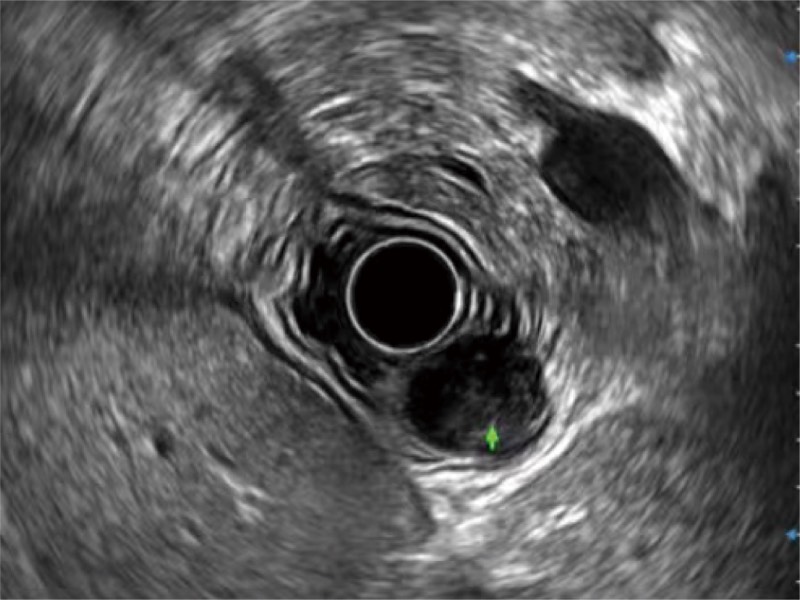

• 微米成像 (μ-Scan)

微米成像技术提升了对组织斑点噪声信号的抑制能力,并进一步强化边界信息,从而获得信噪比更优、边界更清楚锐利的图像

• 食管内间质瘤清晰显像